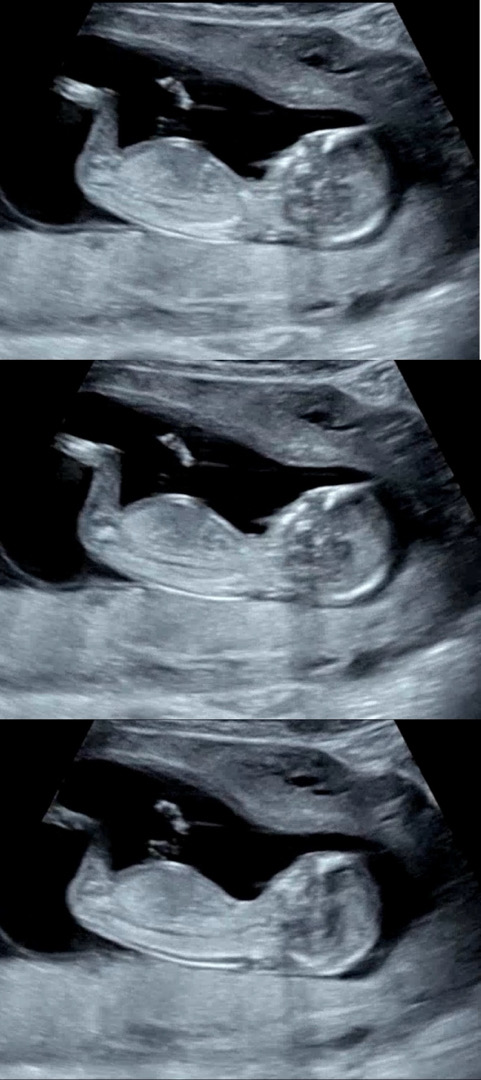

이 사진들로 각도법 될까요??

눈을 크게 떠도 감아도 저는 모르겠습니다....

다리에 가려져서 안보입니다 ㅠㅅㅠ